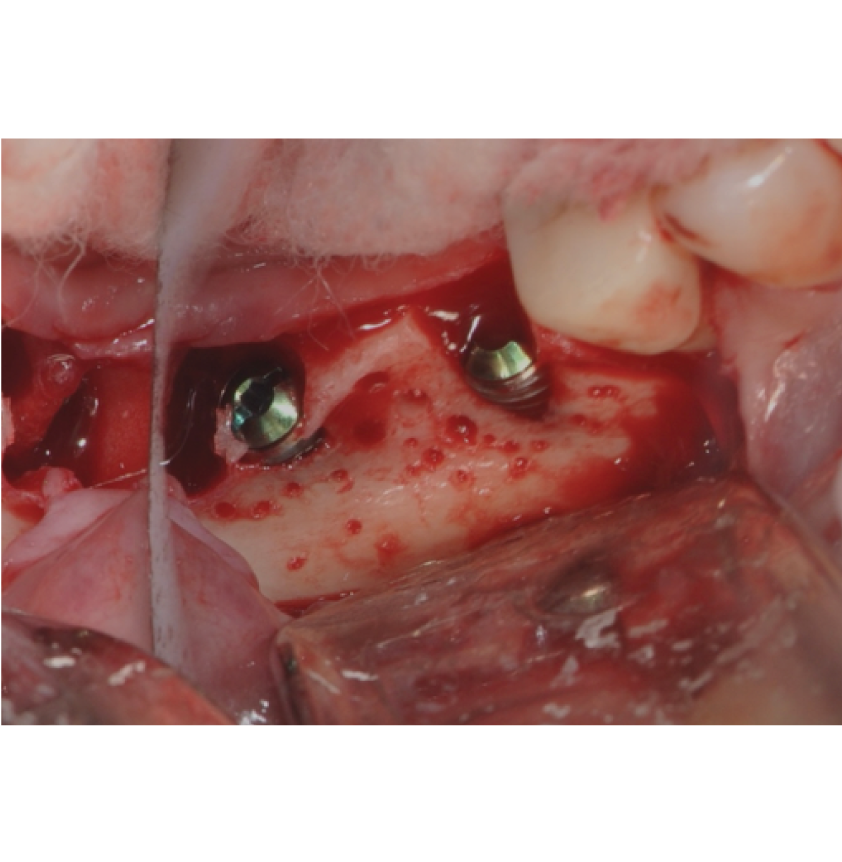

Director’s Clinical Cases

Director’s Clinical Cases

• Case presentations: Clinical pearl from real-world cases

• Case Presentations: Clinical Pearl and must-know takeaways